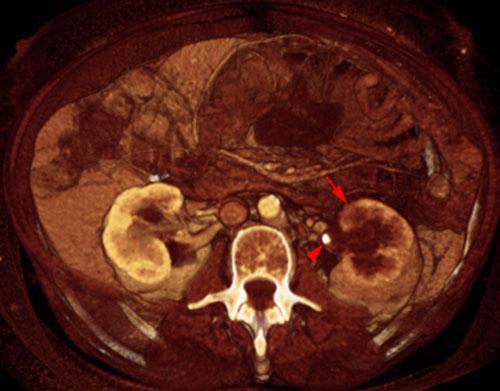

Las lesiones infecciosas del parenquima renal pueden ser visualizadas en fases agudas o como lesiones residuales en fase crónica.

Las lesiones agudas si son pequeñas pueden pasar desapecibidas en la fase coticomedular, identificándose mejor en la fase excretora.

Deben ser estudiados el tamaño renal, área perirrenal, contornos renales, densidad del parénquima renal, cálices renales y distancia corticomedular en estrecha correlación con la clínica del paciente.